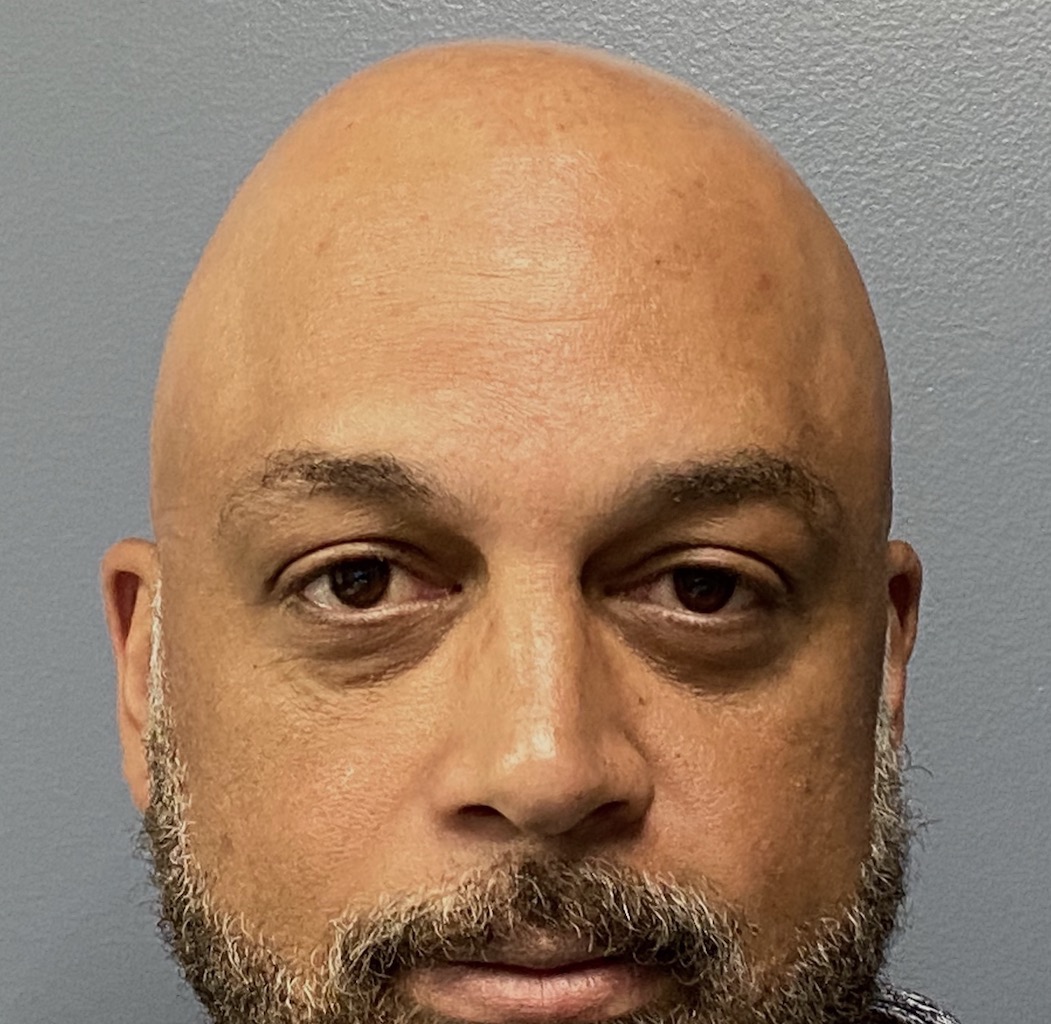

Patient 100

Desire for reshaping of an asymmetric flat back of the head in a shaved head male.

A combined back of the head reshaping procedure was done with a custom skull implant, sagittal ridge reduction and a right temporal muscle reduction.

Desire for reshaping of an asymmetric flat back of the head in a shaved head male.

A combined back of the head reshaping procedure was done with a custom skull implant, sagittal ridge reduction and a right temporal muscle reduction.